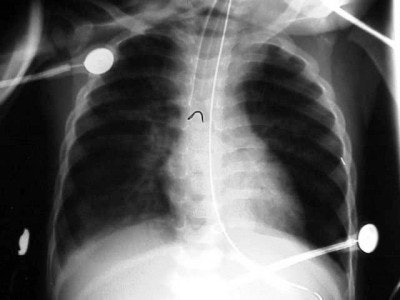

![]() |

| Figure 6 |

| Figure 7 |

| Figure 8 |

In figure 6 we have a 24-month-old who has been intubated, with a diagnosis of RSV. The film is slightly overpenetrated as we cannot clearly make out lung markings, but we can see the bronchial air shadow and the tip of the ETT (marker arrow), which is right at the carina (the bifurcation of the right and left mainstem bronchus). Doctors attempted to re-position the ETT and the left lung is ruptured causing a tension pneumothorax (arrow, figure 7).